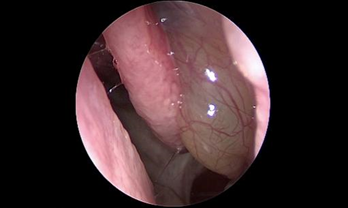

- Phát hiện sớm các trường hợp polyp mũi xoang, ung thư vòm họng qua nội soi.

- Phẫu thuật nội soi mở dẫn lưu các xoang sàng, hàm, trán, bướm điều trị viêm xoang mạn tính

- Phẫu thuật nội soi cắt polyp mũi

- Phẫu thuật nội soi mũi xoang điều trị các viêm xoang đặc biệt: viêm xoang do nấm, viêm xoang do răng

- Phẫu thuật nội soi mũi xoang điều trị các khối u: u nhú mũi xoang, u nhầy.

- Phẫu thuật nội soi mũi xoang với hệ thống định vị trong lúc mổ (Navigation) cho phép bác sĩ tiếp cận trực tiếp đến các vùng mũi xoang bị viêm, gia tăng khả năng quan sát các mốc giải phẫu trong hốc mũi để đánh giá một cách chính xác các bệnh lý sâu trong hốc mũi.

- Trên cơ sở đó, bác sĩ có thể dễ dàng thao tác loại bỏ sạch các tác nhân gây viêm và mủ mà vẫn bảo tồn tối đa niêm mạc lành và hạn chế nạo bỏ niêm mạc triệt để, tối ưu lưu thông không khí trong hệ thống xoang.